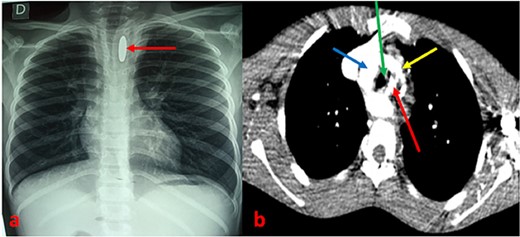

A 13-year-old patient was referred from a peripheral health center to the ENT department of the CHU Sylvanus Olympio for better management of hematemesis due to an esophageal foreign body. He presented with dysphagia to solids and progressive weight loss secondary to accidental ingestion of a coin 6 months previously, which he had not reported to his parents. With the onset of a chronic cough without sputum and moderate hematemesis, he was taken to a peripheral health center, where a chest X-ray revealed a metallic opacity with a large longitudinal axis in the enlarged upper mediastinum and a narrowing of the thoracic trachea (Fig. 1a). In his history, the parents reported a notion of undocumented intermittent dysphagia to solids, yielding spontaneously, evolving since early childhood but worsening in the last few months. On admission, the child’s temperature was normal, he had delayed weight and height, his general condition was preserved, and his hemodynamic status was stable. Examination of the cardiovascular, pleuropulmonary, and digestive systems was unremarkable. A few hours after admission, the patient presented with profuse hematemesis and hemorrhagic shock, which was compensated by transfusions of packed red blood cells. A thoracic CT scan with contrast injection was ordered to understand the mechanism of blockage of the foreign body, to assess its relationship with neighboring organs, and to understand the occurrence of haematemesis. This revealed that a round metallic foreign body, ~2.5 cm in diameter, embedded in the hypertrophied oesophageal muscle, at the level of the 3rd and 4th thoracic vertebrae, in a double aortic arch oesophageal stenosis with a right arch predominantly retro-oesophageal (Fig. 1b).

(a) Chest X-ray showing an opacity related to a metallic foreign body in an enlarged mediastinum with narrowing of the thoracic trachea. (b) CT scan section showing a metallic foreign body embedded in the esophagus associated with a double aortic arch. Arrows: red (esophageal foreign body), blue (right arch), green (trachea), and yellow (left arch).